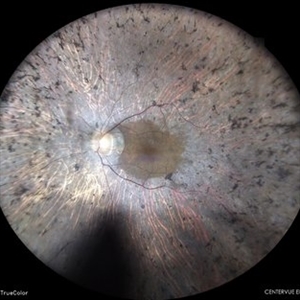

IOL in Vitreous Cavity Right Eye

Fundus infra-red image of a 47-year-old male with IOL in vitreous cavity right eye.

Photographer: Dr. Akansha Sharma-Retina Foundation, Ahmedabad

Condition/keywords: intraocular lens (IOL)